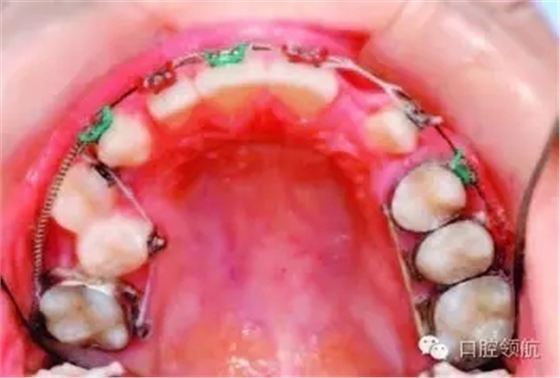

圖2.25中使用的是什么矯治方法?

圖2.25

● 0.018不銹鋼圓絲。

● 上頜右側(cè)用推簧推出前磨牙間隙。

● 前磨牙舌側(cè)粘結(jié)舌鈕,用橡皮鏈改扭轉(zhuǎn)。

● 橡皮鏈通過腭側(cè)的連接桿連接至UL6、UL5和UL4,加強(qiáng)固位。

● UL1、UR1和UR2連扎為一體,用橡皮鏈牽引UL2至正位,鄰接UL1,為UL3提供位置。